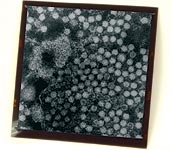

PCV2 observé au microscope électronique. Par sa taille (16 à 18 nm) c’est l’un des plus petits virus animaux.

(Photo cédée par le Dr. Dirk Soike, Landesamt für Verbraucherschutz und Landwirtschaft orbereich, Allemagne) |